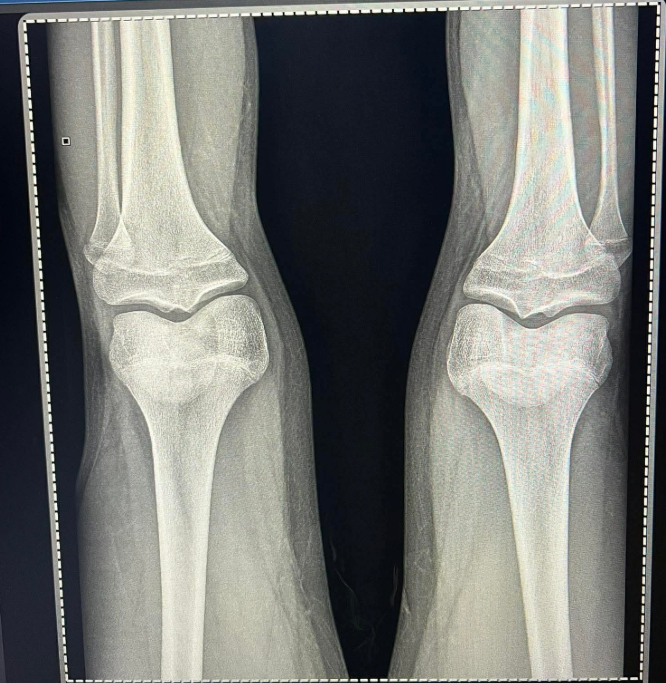

how much more can i grow ? based on this xrays

i have been diganosed like 2 months ago and been on gh for 2 weeks